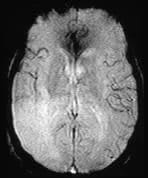

A patient presents with an extensive middle cerebral artery territory infarct.

The MRA demonstrates complete occlusion of the right internal carotid artery (ICA). The perfusion sequence shows prolonged mean transit time in the right frontal area, indicating a delay in the transit time of contrast media as a result of the right ICA stenosis.